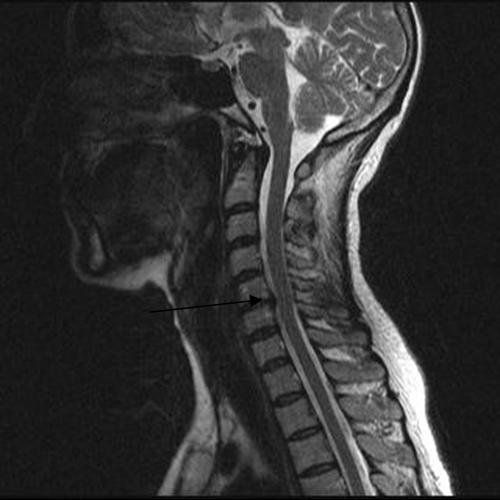

Radyolojik Görüntüler